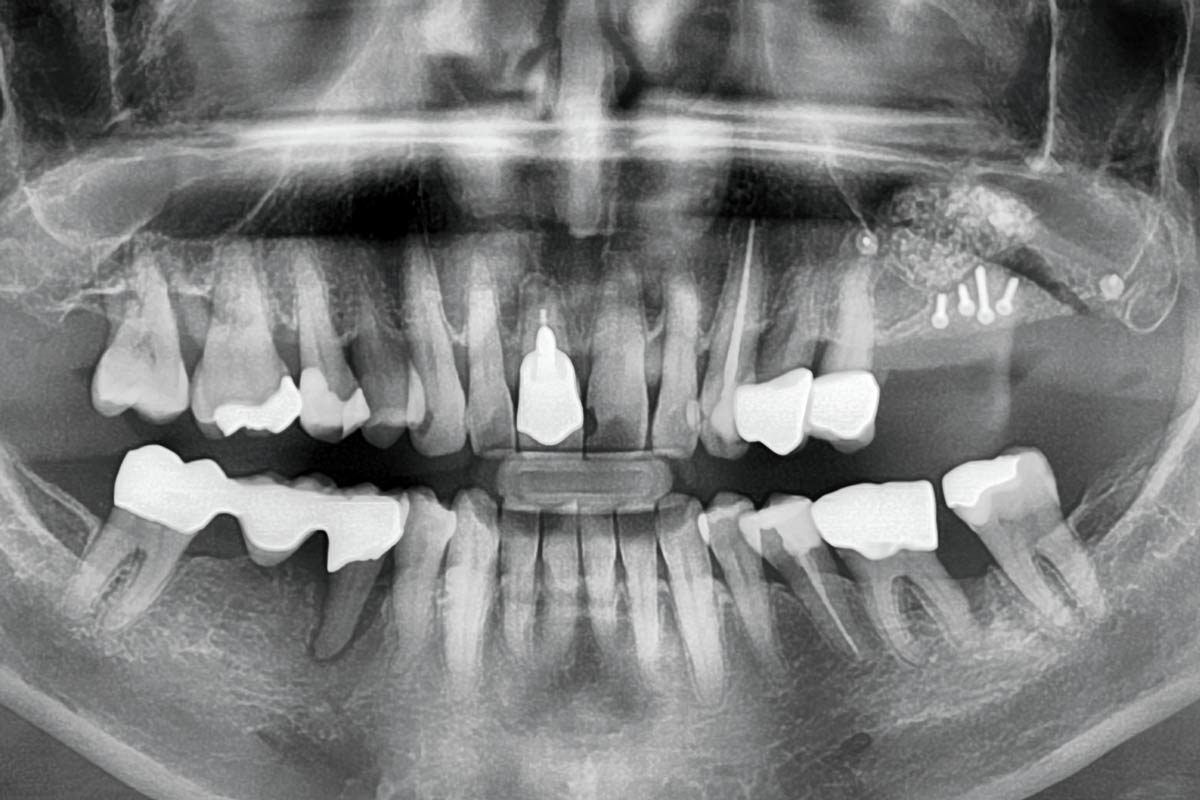

2/15 - Preoperative OPG displaying the vertical bone defectTreatment of a combined horizontal and vertical bone defect in the maxilla with maxgraft® cortico in the allogenic shell technique - Dr. R. Würdinger